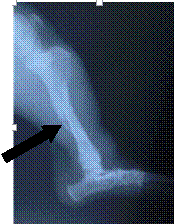

流浪犬髂骨骨折,箭头所示为骨折处。